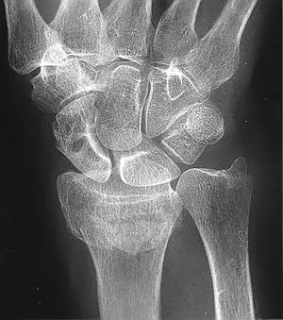

Colle’s Fracture

- Extra-articular fracture of the distal radius with dorsal and radial displacement of the wrist “Dinner fork” deformity

- Seen in elderly with osteoporosis

- Caused by falling on the outstretched hand

Treatment

- Undisplaced : Cast alone

- Displaced: (Sedation/ UGA / ULA), closed reduction, casting Wrist immobilized in flexion & ulnar deviation